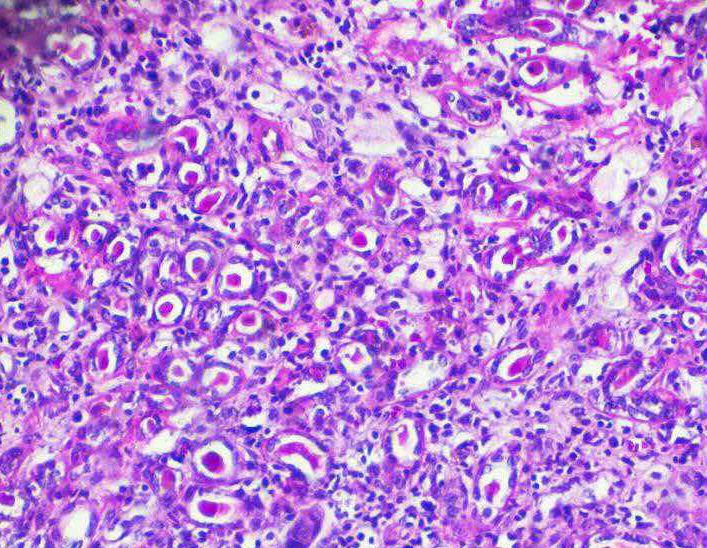

建立一种稳定、可实时监测的胶质瘤原位移植瘤裸鼠模型...